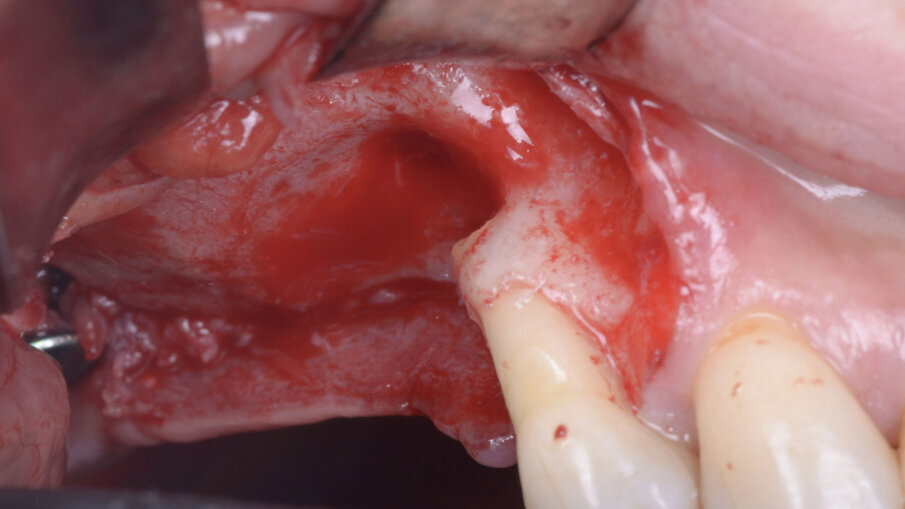

Pertanto, in anestesia locale, si esegue un’incisione a busta in sede 1.8-1.4 con scarico mesiale, si scheletrizza il mascellare superiore isolando per via smussa la deiscenza del pavimento sinusale in sede 1.5 (Fig. 3), e si procede all’estrazione del dente 1.4 e dell’impianto 1.7 ed alla degranulazione dei difetti post-estrattivi. Segue pertanto una opercolizzazione ossea in sede 1.6, con scollamento della membrana di Schneider e creazione di uno spazio subsinusale esteso fino alla deiscenza in 1.5 (Fig. 4). Segue quindi un primo apporto di Regenfast sul letto osseo ricevente e il riempimento dello spazio subsinusale con Geistlich Bio-Oss (Geist-lich Pharma) granulometria small. Segue la stabilizzazione vestibolare di una membrana Geistlich Bio-Gide (Geistlich Pharma) con pins in titanio, e il posizionamento di Geistlich Bio-Oss a ricostruzione del difetto in sede 1.5 ed 1.4. La membrana viene quindi ribattuta sull’aspetto palatale della cresta, e stabilizzata con una combinazione di pin in titanio e suture a materassaio palatali.

Fig. 3 - Scheletrizzazione del lembo, visione vestibolare.

Fig. 4 - Opercolizzazione ossea e scollamento della membrana di Schneider.